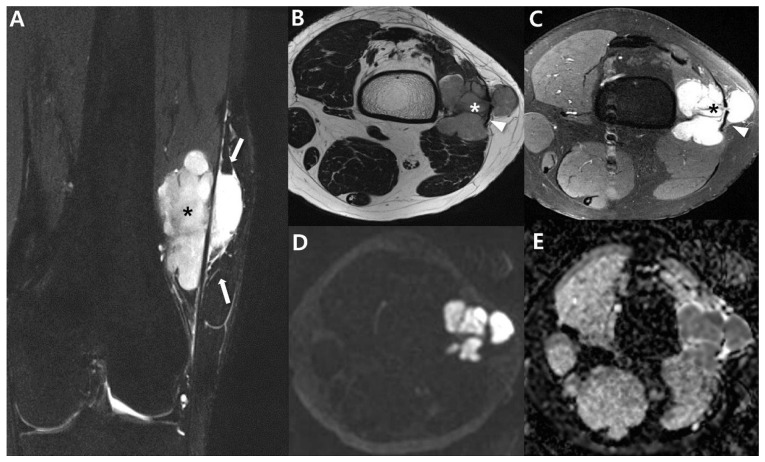

Hallazgo radiológico característico

- ✅ Imagen clave: RM con contraste para estadificación local (extensión, fascias, vasos/nervios) y TC de tórax para metástasis pulmonares en sarcomas de riesgo.

- 🔹 RM con contraste: técnica de elección para estadificación local (tamaño real, compartimentos, fascias, vasos/nervios, “skip lesions” en trayectos).